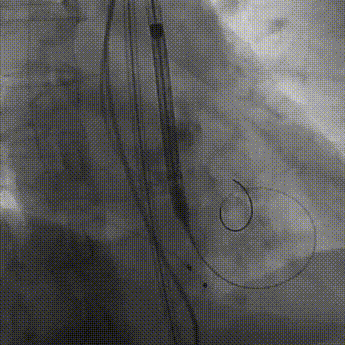

彭小平教授 南昌大学第一附属医院 不断探索医疗可能,筑牢患者长期保障 TAVR 治疗的终极目标,不仅是完成一次手术,更是为患者构建长期稳定的生命保障,而瓣膜耐久性是直接关乎患者后期是否需要二次手术的关键所在。全球首款预装干瓣的问世,为临床提供了全新的选择方案。厂家的15 年质保承诺,是源于材料研发的突破与临床验证的底气。从临床角度,如未来瓣膜可以耐久15年,则可大大减少患者反复就医的身心负担与经济压力,本质上是为患者的长期健康 “投保”。 人生的每一次选择,都需要慎重。相信在行业的前行中,我们不断探索医疗的可能性,让每一次治疗都能真正护航患者长远健康! 患者病史 主诉与现病史:3 年前开始出现胸闷、气促,活动后(如上楼、上坡)症状加重,休息后可缓解,当地医院心脏彩超提示主动脉瓣狭窄,未予特殊治疗;2 年前发现血压轻度升高,口服阿奇沙坦片(40mg,每日 1 次)降压,血压控制尚可;近 1 个月胸闷气促症状明显加重,2025 年 10 月 13 日外院心脏彩超提示主动脉瓣重度狭窄,为进一步诊治入院。 既往史:高血压病史 2 年,规律服用阿奇沙坦片(40mg qd);1 年余前因外伤致腰椎骨折,保守治疗后痊愈;有慢性阻塞性肺疾病病史;有胃窦糜烂、十二指肠球部溃疡史,2023 年曾发生急性上消化道出血;有真菌性食管炎、多发性结肠息肉病史。 术前超声提示:主动脉瓣钙化,主动脉瓣狭窄(重度),左室肥厚,升主动脉增宽。 二尖瓣反流(轻度),三尖瓣反流(轻度),肺动脉瓣高压(轻度)。 左室舒张功能减低,收缩功能正常,左室射血分数 74.7%。 术前CT:Type0型二叶瓣,瓣叶增厚并极重度钙化,钙化主要分布在瓣叶基底部,延伸到左室流出道。主动脉瓣环径24.8mm;升主动脉狭窄后扩张至主动脉弓,双侧瓣叶开口高度可,窦部空间可,STJ内径增宽,升主动脉内径可,预估冠脉低风险;主动脉水平夹角49.1°,非横位心;主动脉弓角、弓距可;“自杀左室”,建议术前补液,ECMO湿备,术中注意循环崩溃。 外周双侧入路内径可,髂总动脉有零星散状钙化,双侧股动脉均能通过20F大鞘,右股低分叉。 手术策略:推荐使用右侧股动脉为主入路,左侧股动脉为辅助入路;右股分叉上方1cm穿刺;推荐使用18mm球囊预扩,预装AV23瓣膜。 手术过程:在右股动脉穿刺建立通路后,顺利送入大鞘,经食道超声及血管造影确认路径稳定。18mm球囊预扩后评估冠脉灌注良好,后将Prostyle A® AV23瓣膜精准释放于目标位置,20mm球囊后扩,超声显示轻微瓣周漏,术后即刻造影显示无明显反流,峰值压差由术前的80mmHg降至12mmHg,心功能明显改善,患者生命体征平稳。 18球囊预扩无腰无漏 输送器跨瓣顺利 定位 平稳释放瓣膜 20球囊后扩 最终造影,位置良好,轻微瓣周漏 Prostyle A®预装干瓣——助力临床最优化解决方案 1、流入端桶状设计:流入端桶状的设计,锚定迅速,有效减少释放步骤,提升植入稳定性; 2、平衡的收腰设计:二叶瓣小心室患者对瓣膜径向支撑力提出更高要求,Prostyle A®均衡的收腰设计可更好适应小瓣环及不规则瓣口结构,保证了EOA,有效降低了循环崩溃风险,提高瓣膜的耐久性; 3、预装干瓣 便捷顺安:金仕生物专利抗钙化技术运用纳米技术去除组织内的细胞碎片和磷脂,封闭游离醛基,从根本上阻断了瓣膜钙化的多项因素,显著提升了瓣膜的耐久性;同时,相比较传统戊二醛保存方式,干式存储最大限度的保留心包的亲水亲油平衡,还原组织天然曲柔性,进一步保障了瓣叶开合,保证长期耐久性; 专家简介 彭小平 南昌大学第一附属医院(点击查看专家详细简历) · END ·